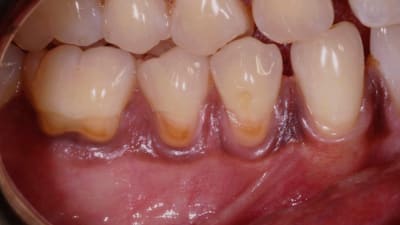

Online Only Periodontics Online Only Preservation of Natural Gingival Pigmentation When Treating Multiple Gingival Recession Defects By Douglas H. Mahn, DDS March 01, 2018 10 min read